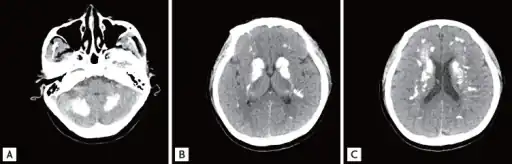

a-c)Brain computed tomography shows diffuse symmetric parenchymal calcifications